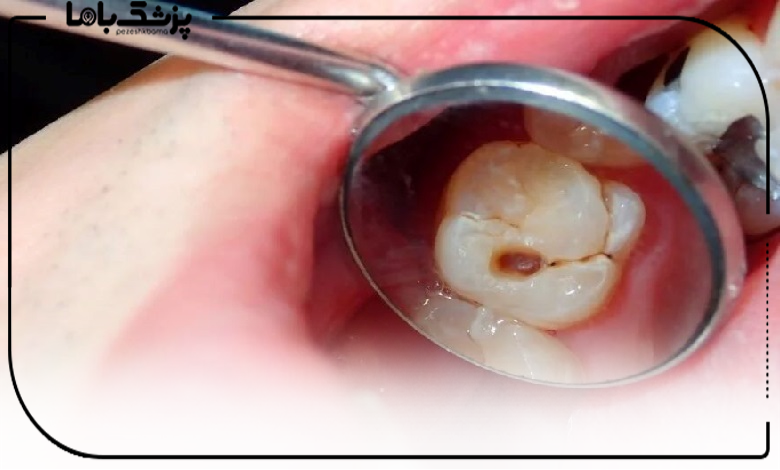

درمان ریشه یا عصبکشی یکی از روشهای حیاتی برای حفظ دندانها از کشیدن شدن است که به دلیل پوسیدگی عمیق یا عفونت دچار آسیب شدهاند. این درمان نیازمند دقت بالا و مهارت تخصصی است که تنها بهترین متخصص درمان ریشه در شهریار آن را دارد. تخصص و تجربه دندانپزشک در تشخیص دقیق، استفاده از تجهیزات مدرن و اجرای مراحل درمان بادقت، ریسک عوارض را کاهش داده و احتمال حفظ دندان طبیعی را افزایش میدهد.

درمان ریشه (عصبکشی) با هدف حذف عفونت و حفظ دندان انجام میشود و اگر توسط بهترین متخصص درمان ریشه انجام شود، با کمترین درد و بیشترین ماندگاری همراه خواهد بود. این درمان معمولاً در یک یا چند جلسه و با تجهیزات دقیق انجام میشود تا از عفونت مجدد جلوگیری شود.